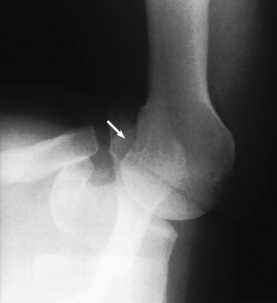

• Anterior dislocation of the humeral head can result in a wedge-shaped compression fracture of the articular surface of the humeral head, called the Hill-Sachs defect.1 The fracture is located on the posterolateral humeral head. An exaggerated external rotation of the arm may be required to see the defect.

Structures shown: An inferosuperior axial image shows the proximal humerus, the scapulohumeral joint, the lateral portion of the coracoid process, and the AC articulation. The insertion site of the subscapular tendon on the lesser tubercle of the humerus and the point of insertion of the teres minor tendon on the greater tubercle of the humerus are also shown. A Hill-Sachs compression fracture on the posterolateral humeral head may be seen using the Rafert modification (Figs. 5-29 and 5-30).

Fig. 5-29 A, Inferosuperior axial shoulder joint: Lawrence method. B, Inferosuperior axial shoulder joint: Rafert modification showing Hill-Sachs defect (arrow). C, Coronal MRI of shoulder joint showing Hill-Sachs defect (arrow) after recurring shoulder dislocation. (A and B, From Rafert JA et al: Axillary shoulder with exaggerated rotation: the Hill-Sachs defect, Radiol Technol 62:18, 1990. C, From Jackson SA, Thomas RM: Cross-sectional imaging made easy, New York, 2004, Churchill Livingstone.)